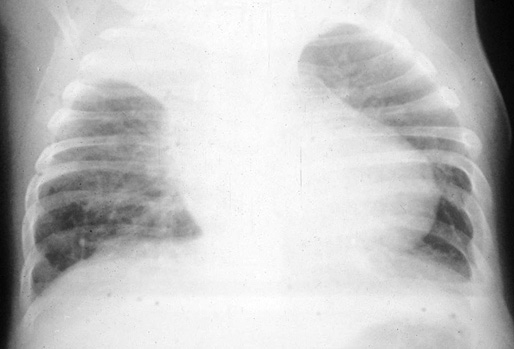

• Neumonía: existe una forma concomitante con la sepsis o la meningitis y otra primaria. Esta no es infrecuente que vaya precedida de una infección vírica de vías respiratorias altas. Su incidencia se desconoce, debido a que su presentación clínica es idéntica a la producida por otros microorganismos. Como en cualquier neumonía, establecer el diagnóstico etiológico es difícil. Suelen ser pacientes mayores de 10 años. La sintomatología suele tener un inicio gradual, con localización más frecuente en los lóbulos inferiores y, habitualmente, sin empiema. El pronóstico en general es bueno.

En el lactante menor de 3 meses, las formas de presentación más frecuentes son las crisis de apnea y cianosis, o el inicio como una bronquiolitis. Existe una forma clínica en esta edad, con una letalidad muy alta, que se denomina síndrome de la tosferina maligna y se caracteriza por la presencia de hiperleucocitosis importante con: reacción leucemoide, bronconeumonía, hipertensión arterial pulmonar secundaria y shock cardiogénico por fallo miocárdico (Fig. 23). La vacunación sistemática de la tosferina de la embarazada ha disminuido notablemente la incidencia de tosferina maligna.

Figura 23. Síndrome de la tosferina maligna en un lactante de 2 meses ingresado en la UCI y que requirió oxigenación por membrana extracorporea (Cortesía del Hospital Infantil Vall d’Hebron).